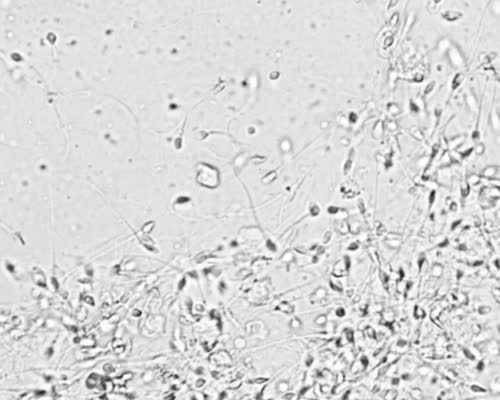

6、不过试管婴儿成功率体现在患者身上只有两种情况,成功or不成功,患者拥有一个良好的身体并且能发育出成熟高质量的精子、卵子才是根本,大家加油!